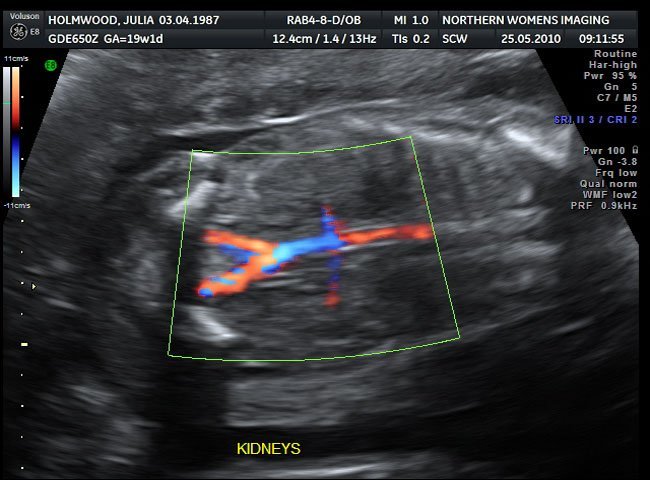

Ecografía Doppler

No es una ecografía de rutina, pero en algunos casos se suele realizar una ecografía con técnica doppler. Se utiliza para medir y evaluar el flujo de sangre que circula a través de las arterias y de las cavidades y válvulas del corazón del bebé.

Se puede ver el flujo de sangre en color, permitiendo detectar de forma precoz cualquier anomalía relacionada con el caudal circulatorio y el funcionamiento del corazón.

También permite evaluar si la circulación sanguínea del cordón umbilical es la adecuada.

Está indicada para controlar los embarazos en los que la madre presenta hipertensión, diabetes, problemas en la placenta o el cordón umbilical, retardo en el crecimiento, sufrimiento fetal, o malformaciones cardíacas del bebé.